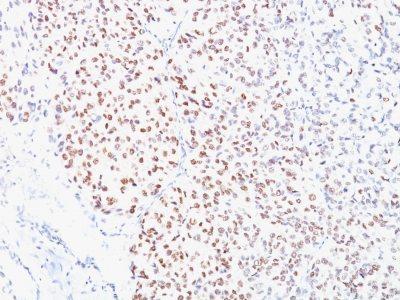

MITF (microphthalmia transcription factor) is a basic helix-loop-helix-leucine-zipper (bHLH-Zip) transcription factor that regulates the development and survival of melanocytes and retinal pigment epithelium, and also is involved in transcription of pigmentation enzyme genes such as tyrosinase TRP1 and TRP2. MITF has been shown to be phosphorylated by MAP kinase in response to c-kit activation, resulting in upregulation of MITF transcriptional activity. Mutations of the MITF gene are associated with the autosomal dominant hereditary deafness and pigmentation condition, Waardenburg Syndrome type 2A. Multiple isoforms of MITF exist, including MITF-A, MITF-B, MITF-C, MITF-H, and MITF-M, which differ in the amino-terminal domain and in their expression patterns. The MITF-M isoform is restricted to the melanocyte cell lineage. Anti-MITF, D5, recognizes a nuclear protein, which is expressed in the majority of primary and metastatic epithelioid malignant melanomas as well as in normal melanocytes, benign nevi and dysplastic nevi.Primary antibodies are available purified, or with a selection of fluorescent CF® Dyes and other labels. CF® Dyes offer exceptional brightness and photostability. Note: Conjugates of blue fluorescent dyes like CF®405S and CF®405M are not recommended for detecting low abundance targets, because blue dyes have lower fluorescence and can give higher non-specific background than other dye colors.

Positive Control

Jurkat, A-431, HeLa or 501 Mel human melanoma cells or Melanoma

Nucleus

Melanocytes

IHC (FFPE) (verified)

Higher concentration may be required for direct detection using primary antibody conjugates than for indirect detection with secondary antibody|Immunofluorescence: 0.5-1 ug/mL|Does not react with mouse or rat, others not tested|Immunohistology (formalin)|Staining of formalin-fixed tissues requires boiling tissue sections in 10 mM citrate buffer, pH 6.0, for 10-20 min followed by cooling at RT for 20 minutes|Flow Cytometry 0.5-1 ug/million cells/0.1 mL|Optimal dilution for a specific application should be determined by user